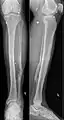

Esquirlas de granada en el tejido blando de la pierna (junto a una vieja fractura de la fíbula).